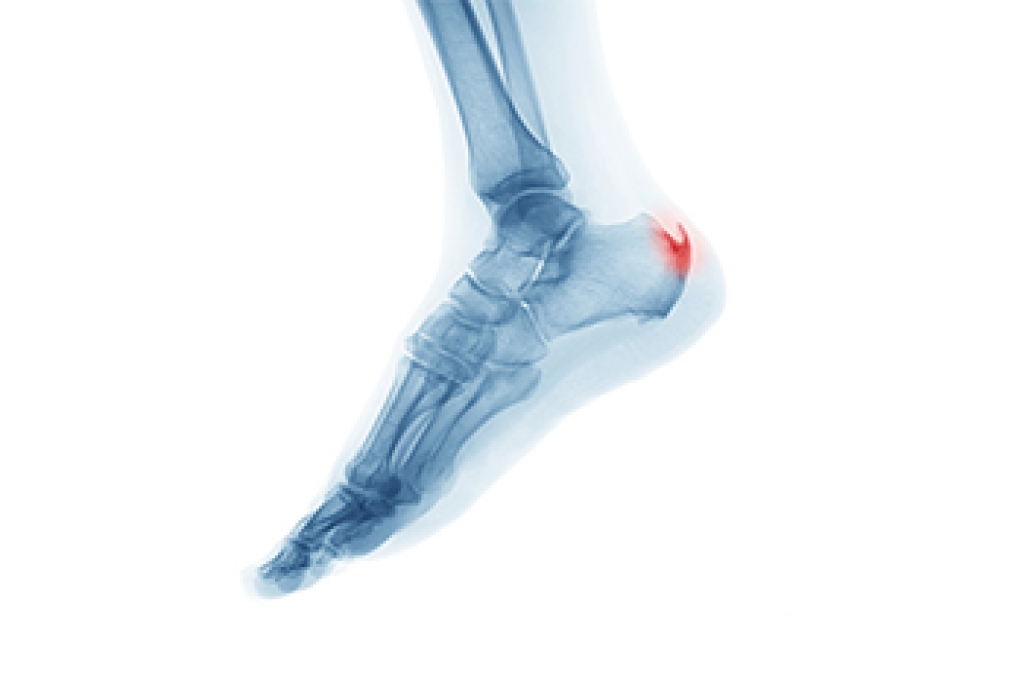

Gout, a complex form of arthritis, is often accompanied by intense pain and inflammation that targets the joints, including the feet. This condition results from the accumulation of uric acid crystals in the joints, leading to sudden and excruciating attacks of pain. The underlying cause is often an overproduction or inefficient excretion of uric acid, which is a waste product. Dietary factors, such as high purine foods and excessive alcohol consumption, can exacerbate gout. Managing gout involves implementing various treatment methods. Medications may help to reduce pain and inflammation during attacks, while long term strategies focus on lowering uric acid levels. This can be accomplished through lifestyle adjustments and prescribed medications. Consulting a podiatrist is paramount in tailoring an effective treatment plan. If you are afflicted with gout, it is strongly suggested that you are under the care of this type of doctor who can effectively help you to manage this condition.

Gout is a type of arthritis caused by a buildup of uric acid in the bloodstream. It often develops in the foot, especially the big toe area, although it can manifest in other parts of the body as well. Gout can make walking and standing very painful and is especially common in diabetics and the obese.

Gout can easily be identified by redness and inflammation of the big toe and the surrounding areas of the foot. Other symptoms include extreme fatigue, joint pain, and running high fevers. Sometimes corticosteroid drugs can be prescribed to treat gout, but the best way to combat this disease is to get more exercise and eat a better diet.